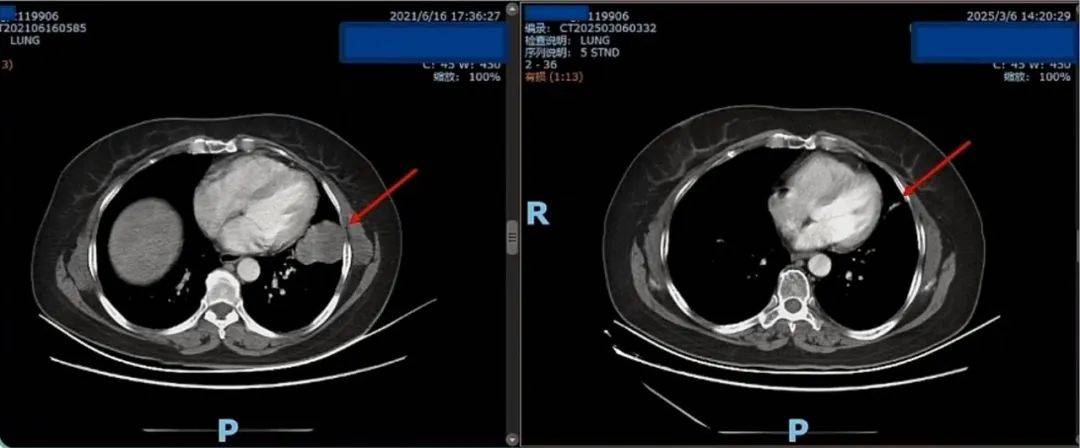

患者为一名56岁女性,2021年4月因胸部增强CT发现左上肺门及舌段肿块就诊,气管镜活检病理确诊肺腺癌。基因检测提示ROS1基因融合,临床分期ⅣA期(伴脑转移)。影像学显示左肺原发灶伴肺门/纵隔淋巴结转移,颅内多发转移灶。

治疗1个月后(2021年8月),肺内原发灶及纵隔淋巴结显著缩小,颅内转移灶消失。

持续治疗至2025年3月,CT复查显示肺内病灶纤维化、钙化,颅内无复发,达到深度缓解。

患者2021年确诊时与2025年用药后的CT结果对比